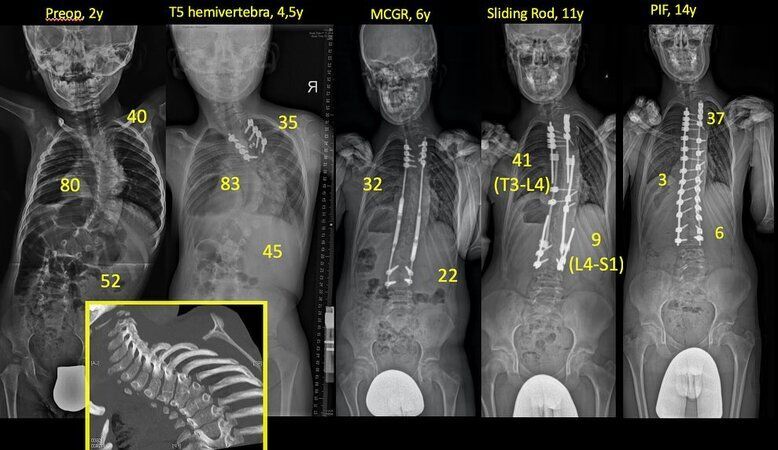

Omurgası eğri olarak dünyaya gelen Kuzey'i dimdik hale getiren Alanay, artık ciddi rahatsızlığından eser kalmayan gencin son durumuna ilişkin "Bu, bir doktor için tarif edilemez bir mutluluk" dedi.

"Kuzey ile ilk tanışmamız, henüz 2 yaşındayken başladı. Şiddetli bir skolyoz deformitesiyle başlayan bu uzun yolculuk, farklı zamanlarda uyguladığımız ameliyatlar ve müdahalelerle sürdü. Amacımız yalnızca eğriliği düzeltmek değil, aynı zamanda Kuzey’in büyümesini de sağlıklı bir şekilde devam ettirebilmekti.

Bugün, tam 13 yıl sonra, 15 yaşındaki Kuzey artık dimdik! Büyümesini tamamladı, skolyozundan tamamen arındı ve boyu bile beni geçti!

Kuzey’in sabrı, ailesinin bana olan güveni ve hep birlikte gösterdiğimiz kararlılık sayesinde, bu zorlu ama başarılı süreci sorunsuz şekilde tamamladık. Artık onun için yepyeni bir dönem başlıyor. Geleceğine daha çok odaklanacağı, sadece skolyoz değil doğuştan gelen tüm sorunları da geride bıraktığı harika bir hayata doğru…